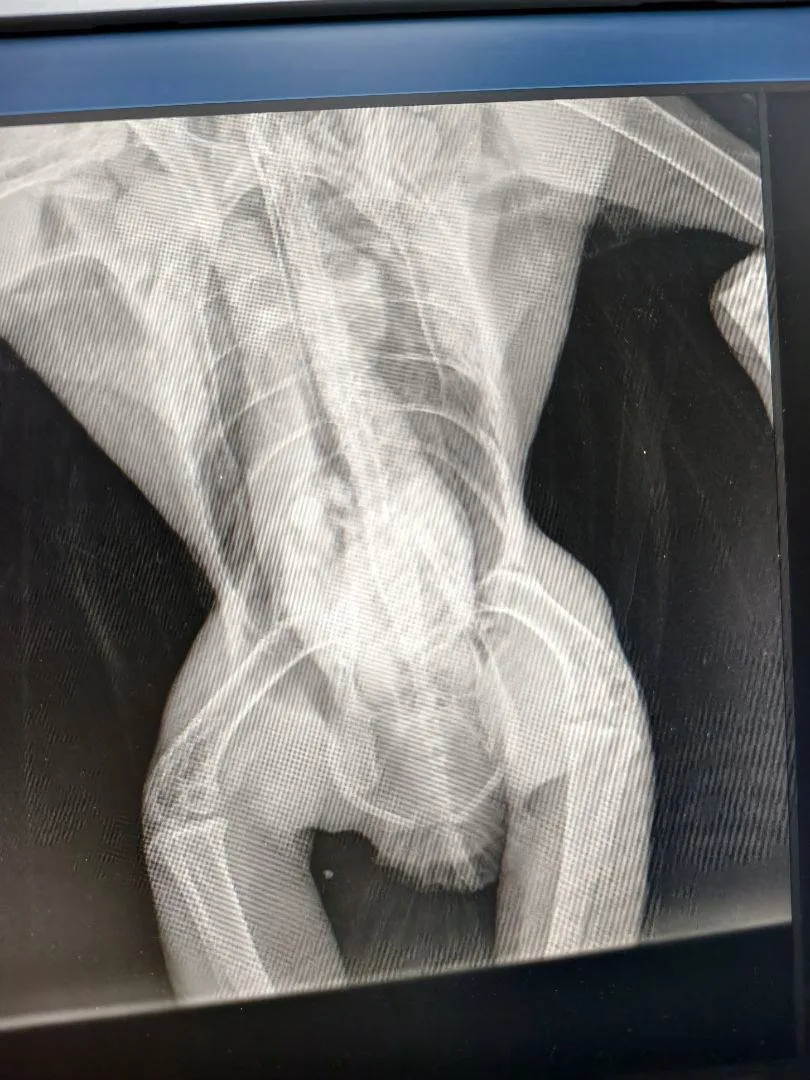

В ростовской клинике смогли поставить верный диагноз пациентке после восьми лет болей

В ростовской клинике «Юнона» смогли поставить сложный диагноз пациентке, которая до этого восемь лет получала неэффективное лечение.

Среди жалоб 37-летняя женщина отмечала боль и отек коленных суставов. Ранее ей назначали лекарственные препараты и даже проводили операцию для лечения разрыва мениска, потому что врачи предположили такой диагноз. Но манипуляции не дали результата.

В «Юноне» пациентка пришла на прием к доктору Ольге Матвеевой, которая выявила синовит коленных суставов. Подобное состояние может возникать как реакция на какое-либо раздражение. Например, инфекцию, травму или аутоиммунное воспаление. Но определить причины синовита может быть затруднительно, как и в этом случае.

У женщины взяли на анализ кровь и синовиальную жидкость, провели МРТ и прочие исследования, но ясности не было. Тогда врачи обратили внимание на слова пациентки, что несколько лет назад у нее был период выраженной боли в левом плечевом суставе, который длился несколько месяцев. МРТ этого сустава показало признаки артрита в виде эрозий и отека. Также пациентка вспомнила, что врач, который делал ей артроскопию несколько лет назад, обнаружил значительное разрастание ворсин синовиальной оболочки коленного сустава.

Собранные выводы указывали на аутоиммунный артрит, но нужно было понять, к какому типу он относится. Медики выполнили диагностическую артроскопию коленного сустава и изучили «синовиальный пейзаж», и это наконец помогло поставить диагноз – периферический спондилоартрит.

А назначенное лечение уже спустя три месяца показало высокую эффективность.